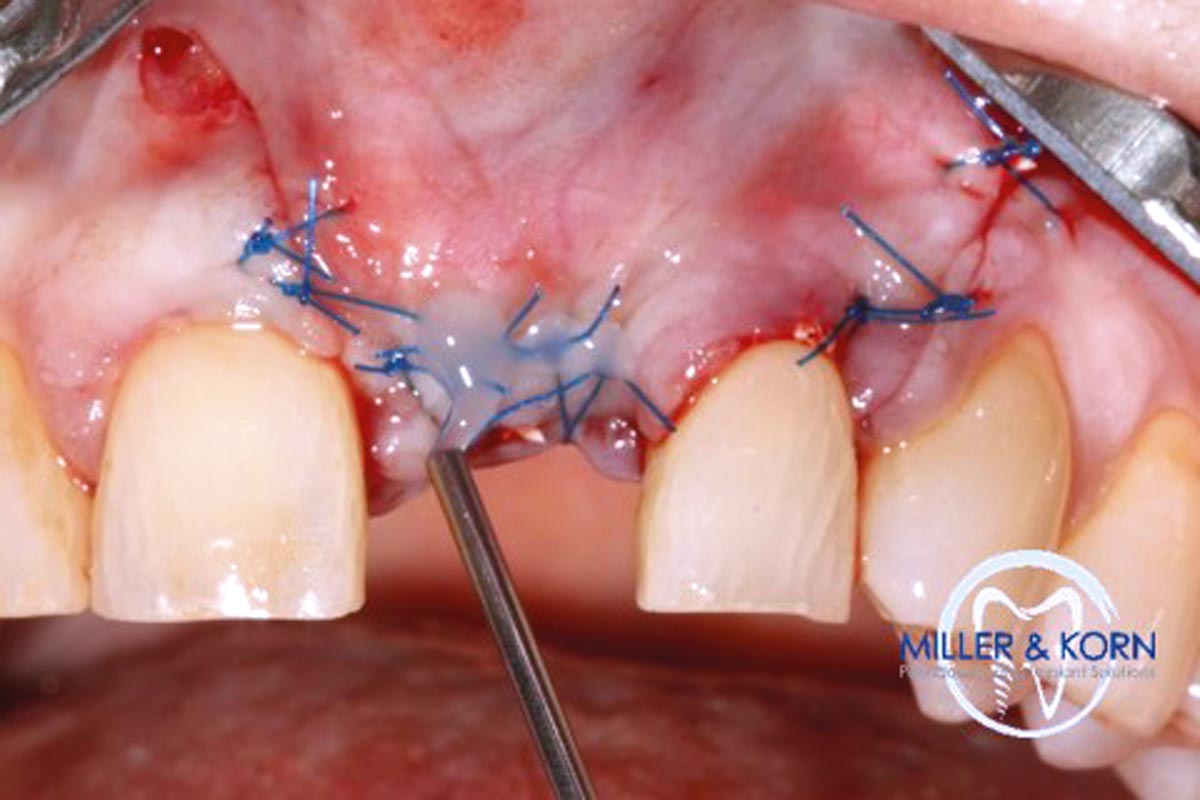

26/39 - Covering of the augmented area with a Jason® membrane sutured to the palatal flapImmediate implant placement and correction of horizontal and vertical bone loss using an allograft bone ring, cerabone® and Jason® membrane - Drs. Miller and Korn

27/39 - Application of Emdogain® on the suturesImmediate implant placement and correction of horizontal and vertical bone loss using an allograft bone ring, cerabone® and Jason® membrane - Drs. Miller and Korn